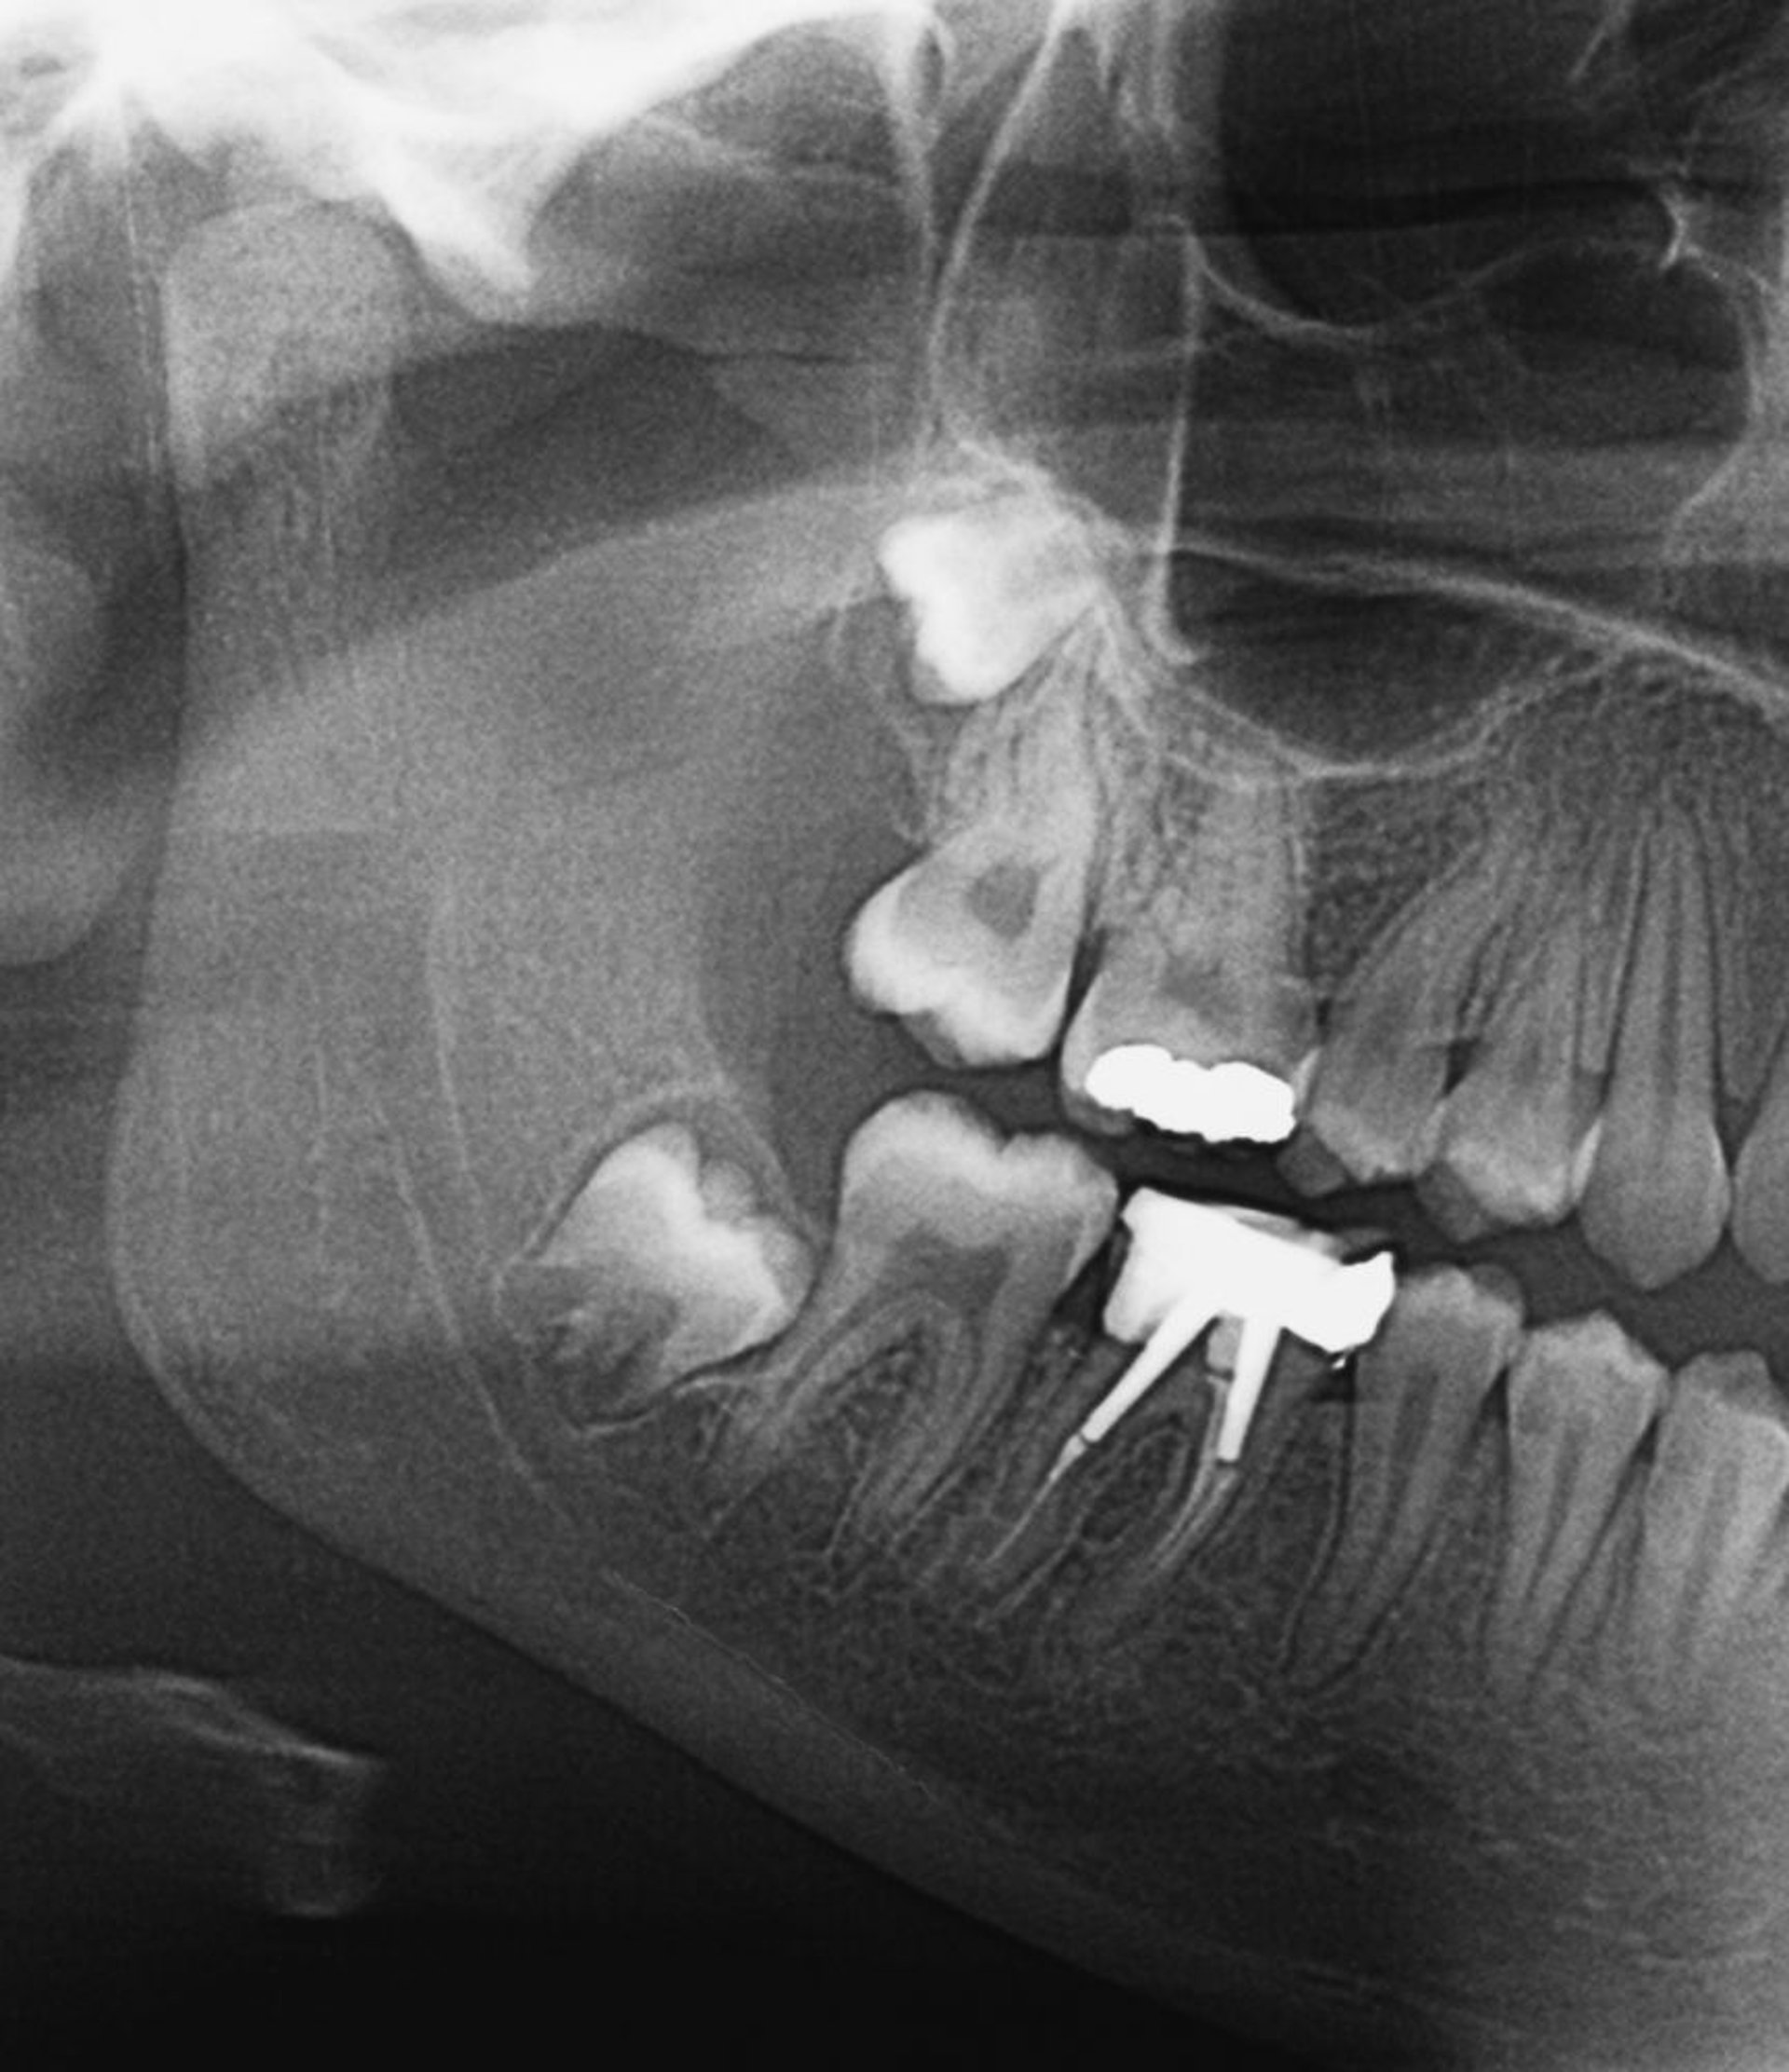

歯科X線が主な検査であるが,これは歯科医師に任せることができる。